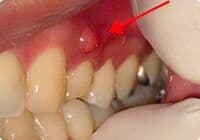

根尖周囲組織に炎症が波及すると、フィステルといわれる排膿路(歯ぐきにポツリとできたおできの様なふくらみ)が形成されることがあります。

無症状で進行する虫歯・原因不明の歯肉の腫れを、コンセプトを守った初回根管治療(精密根管治療)で治癒

歯髄壊死の症例

| 主訴 | 左下奥から2番目の歯(下顎第二大臼歯)が年に数回腫れることがある |

|---|---|

| 治療内容 | 根管治療(抜髄)|精密根管治療 |

| 治療期間 | 1週間 |

| 治療費用 | 181,500円(税込)※支台築造処置を含む |

| リスク・副作用 | ・治療計画は口腔内、歯牙の状況により変更する場合があります。 ・下顎に対するインプラントを含む外科的処置にて下歯槽神経を損傷した場合、顔面に知覚麻痺が生じる場合があります。 ・当院の補綴処置の保証期間は5年間ですが、3ヶ月〜6ヶ月の定期的なメインテナンス、定期検診に来院されていない場合は適用されません。 |